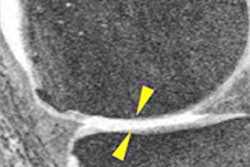

MR images of the right knee show signal abnormalities at baseline and subsequent defects at the 48-month follow-up. Above image shows a hyperintense signal abnormality in the patella at baseline (arrow). Image below shows the development of a fissure in the same patient (arrow) at 48 months. Images courtesy of Radiology.In an analysis by compartment, data revealed that cartilage signal abnormalities were most frequent in the patella (44 cases, 35%), followed by the lateral tibia (33 cases, 26%), trochlea (31 cases, 25%), medial femur condyle (10 cases, 8%), lateral femur condyle (7 cases, 6%), and medial tibia (1 case, 1%).